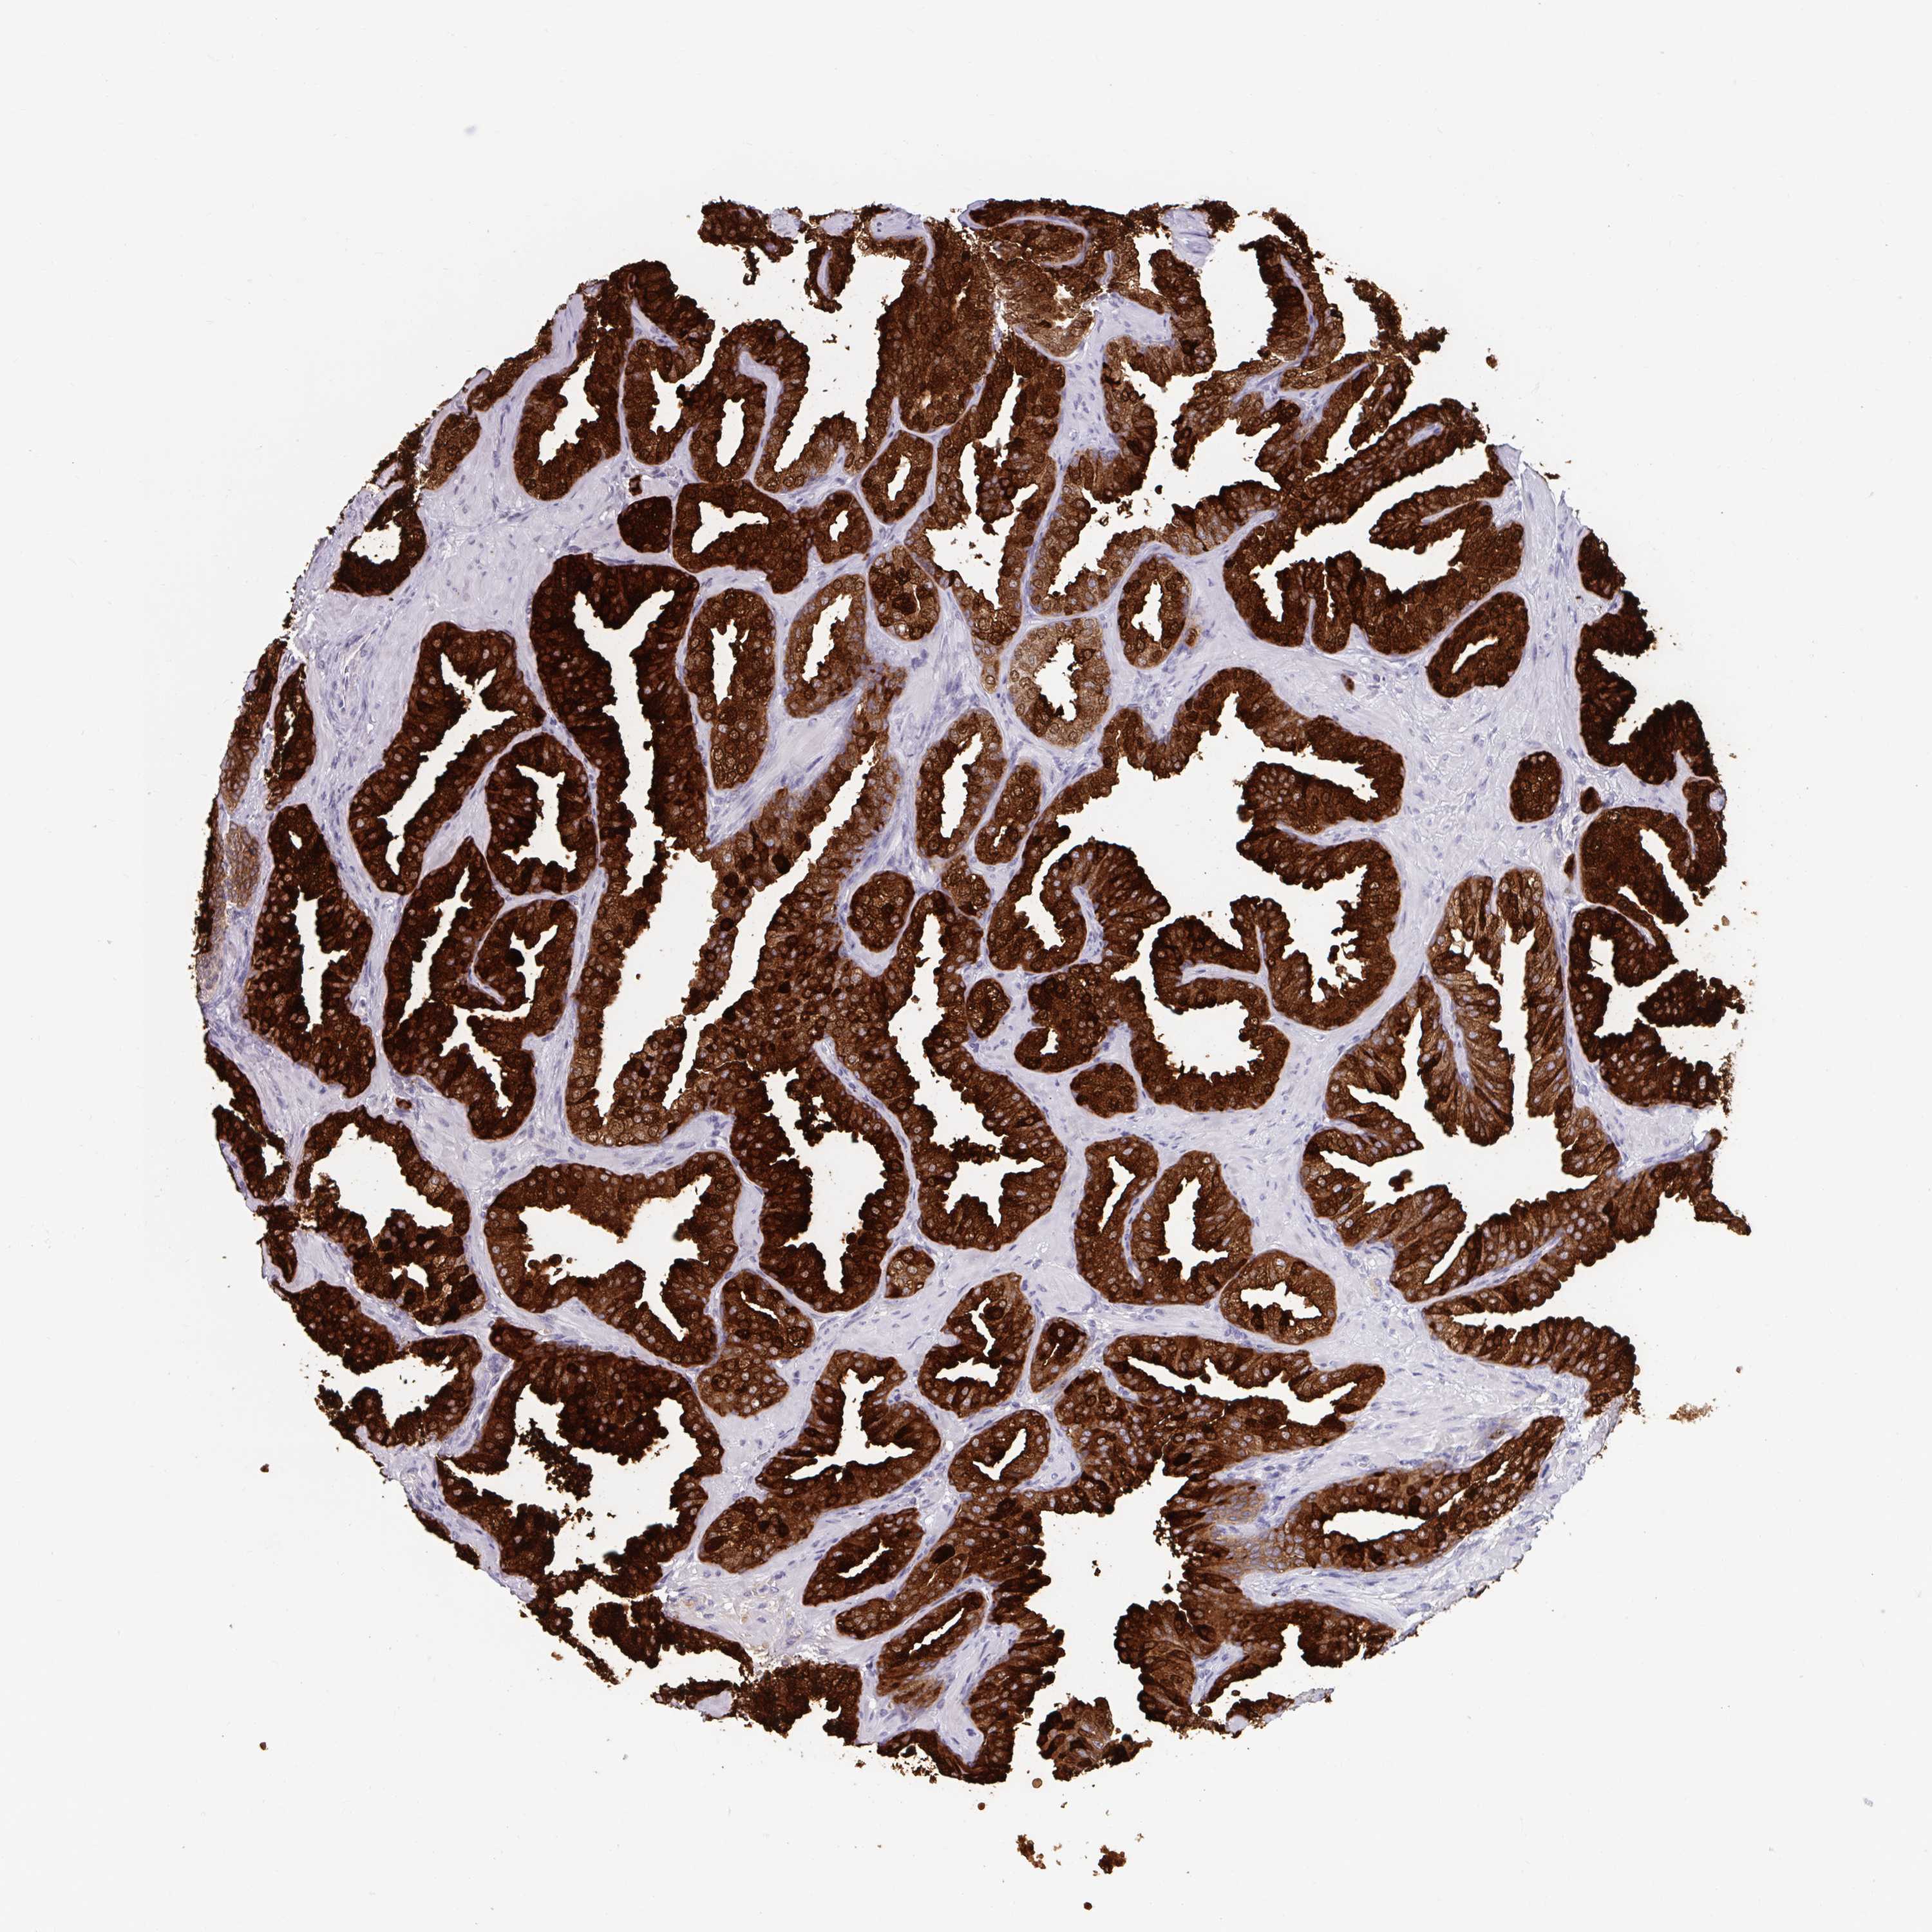

PROSTATE CANCER - Protein expressioni

A mouse-over function shows sample information and annotation data. Click on an image to view it in a full screen mode. Samples can be filtered based on level of antibody staining by selecting one or several of the following categories: high, medium, low and not detected. The assay and annotation is described here.

Antibody stainingi

Antibody staining in the annotated cell types in the current human tissue is reported as not detected, low, medium, or high, based on conventional immunohistochemistry profiling in selected tissues. This score is based on the combination of the staining intensity and fraction of stained cells.

Each image is clickable and will lead to virtual microscopy that enables deeper exploration of all samples and also displays staining intensity scores, fraction scores and subcellular localization as well as patient and tissue information for each sample.

Antibody HPA051257

Antibody CAB026357

Staining

High

Medium

Low

Not detected

Intensity

Strong

Moderate

Weak

Negative

Quantity

>75%

75%-25%

<25%

None

Location

Nuclear

Cytoplasmic/membranous

Cytoplasmic/membranous,nuclear

Adenocarcinoma, High grade

Adenocarcinoma, Medium grade

Adenocarcinoma, Low grade